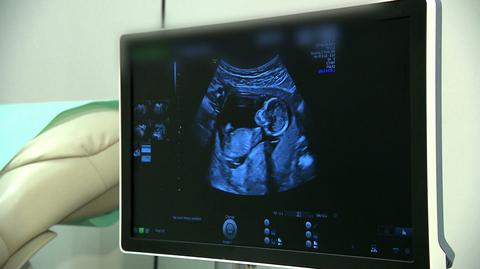

Jak mam starać się o dziecko bez strachu? Czy będę mogła liczyć na badania prenatalne? Kobiety pytają, bo nie wiedzą, co będzie dalej. Podczas planowania rodziny chcą szczęścia, a nie koszmaru, a w razie poważnego problemu - fachowej pomocy, a nie lekceważenia.

Od kilku dni setki par marzących o dziecku zastanawiają się, czy będą miały dostęp do badań prenatalnych, a jeśli tak, to czy lekarz, nad którym wisi groźba więzienia, poinformuje rodziców, że wyniki tych badań są złe.

- Nie wiadomo, czy w ogóle będą badania prenatalne. Jaki jest ich sens? - pyta prof. Marian Szamotowicz z Kliniki Rozrodczości i Endokrynologii Ginekologicznej Uniwersytetu Medycznego w Białymstoku.

- Kobieta dowie się o wynikach badań prenatalnych tylko wtedy, kiedy będzie możliwość leczenia wewnątrzmacicznego czy też leczenia tuż po urodzeniu - ocenia Krystyna Kacpura z Federacji na rzecz Kobiet i Planowania Rodziny.

- Może dochodzić do przypadków, kiedy kobiety nie będą kierowane na takie badania, kiedy nie będzie się im mówiło prawdy o wynikach tych badań, w związku z czym dowiedzą się dopiero przy porodzie, że płód obarczony jest taką ciężką i nieodwracalną wadą - dodaje Kamila Ferenc z Federacji na rzecz Kobiet i Planowania Rodziny.

Wiedza dotycząca wyniku badania prenatalnego jest szczególnie ważna dla kobiet, które zachodzą w ciążę w późnym wieku, na przykład po latach leczenia niepłodności.

O ile wada płodu nie jest ciężka i nieodwracalna, to badania prenatalne pozwalają zaplanować leczenie. Albo jeszcze w trakcie ciąży, albo od razu po porodzie.

- Jeżeli nie będziemy robili badań prenatalnych, te dzieci będą się rodziły nie tam, gdzie trzeba, nie wtedy, kiedy trzeba, nie w taki sposób, w jaki trzeba. Ich szanse na przeżycie, na prawidłowy rozwój, będą przez to ograniczone - ocenia profesor Mirosław Wielgoś, konsultant krajowy w dziedzinie perinatologii.